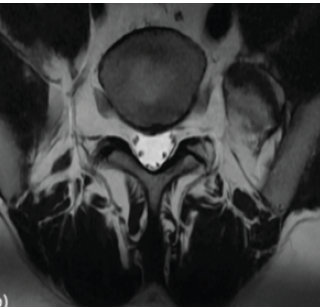

Harnessing 3D Printing Technology for Complex Acetabular Reconstruction in Revision Total Hip Arthroplasty: From Childhood Hip Trauma to Customized Modern Solutions